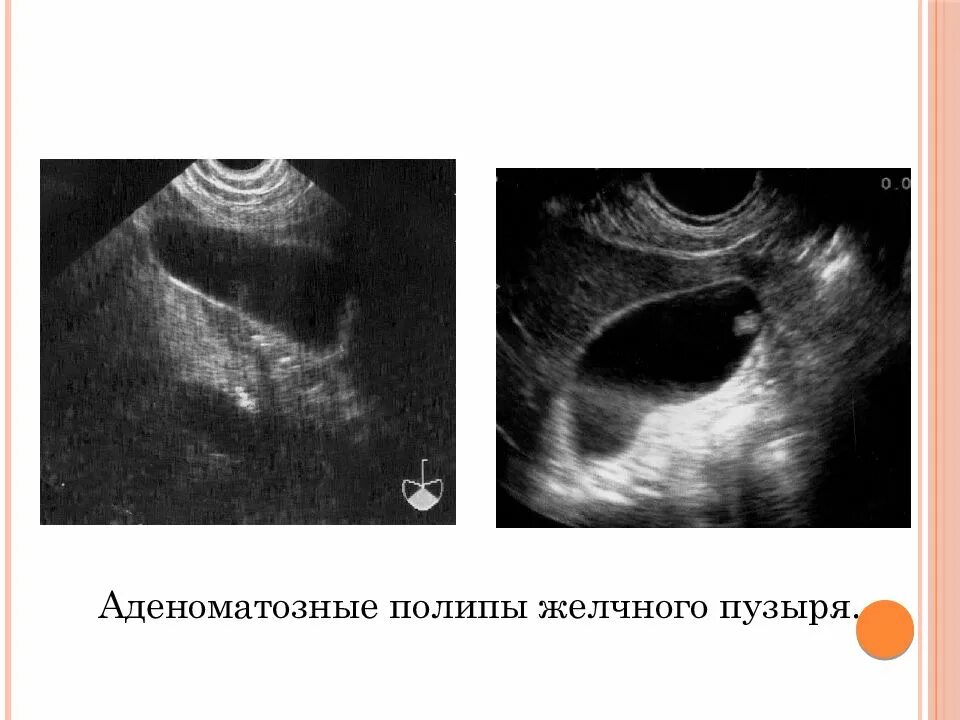

Полипы в желчном пузыре симптомы и лечение